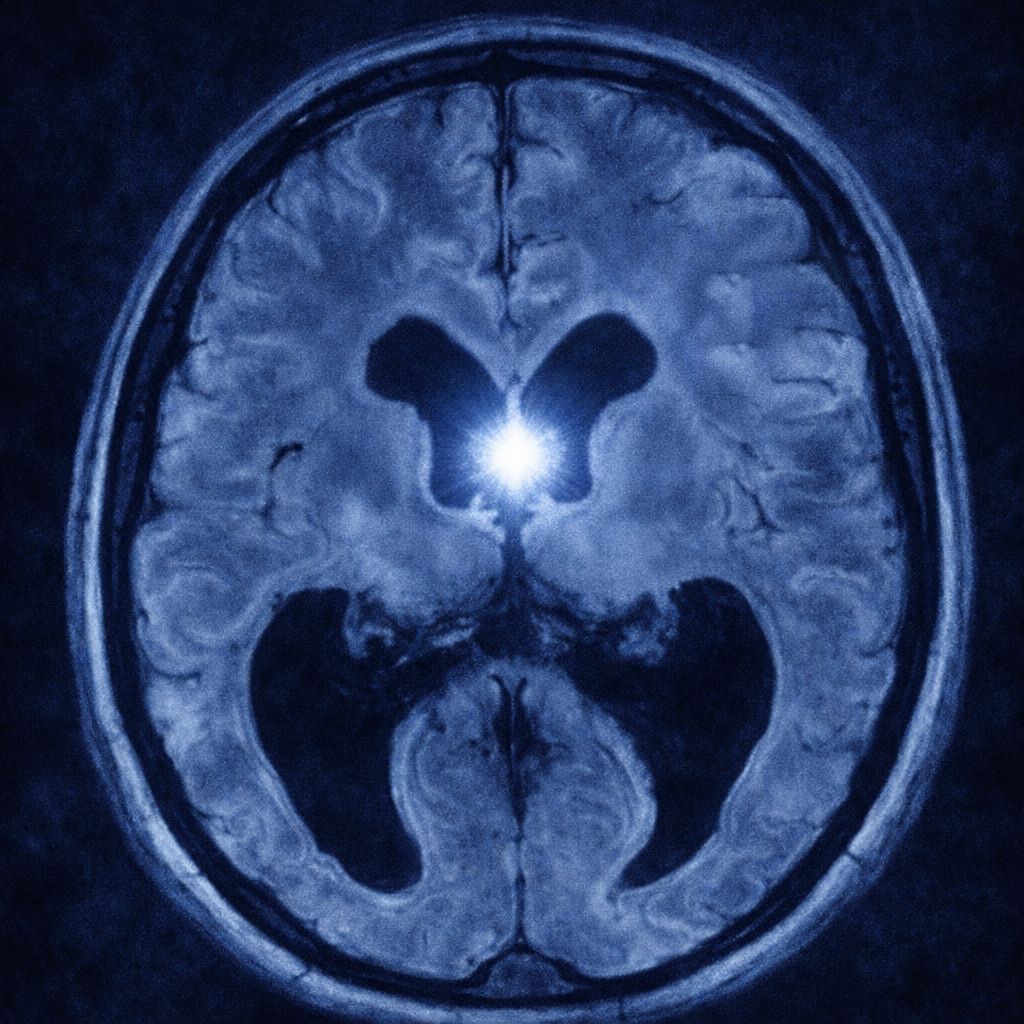

Quiste coloide

El quiste coloide es una lesión benigna que se forma en el cerebro, específicamente en el tercer ventrículo, una cavidad que contiene líquido cefalorraquídeo (LCR). Está compuesto por una cápsula fina que rodea un material gelatinoso llamado coloide. Aunque es una condición poco frecuente, puede causar síntomas graves si bloquea el flujo normal del LCR, lo que provoca hidrocefalia y aumento de la presión intracraneal. En la mayoría de los casos, el quiste coloide se detecta en adultos jóvenes y suele crecer lentamente.

• Resonancia magnética (RM): permite visualizar el tamaño, ubicación y características del quiste.